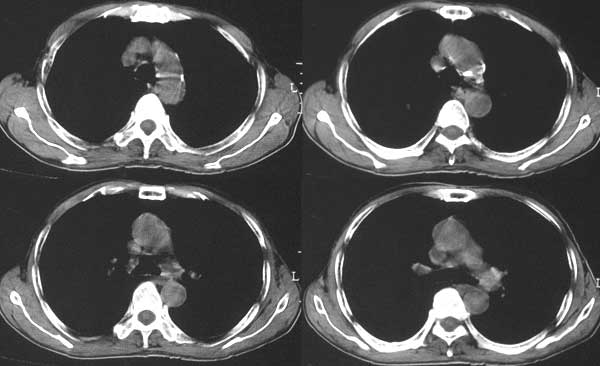

本例病人肺内多发结节灶、双侧肋骨破坏、胸椎椎体及椎弓破坏应是肾癌转移。请大家分析气管内结节灶性质?另外还得麻烦领导给删掉那多余的那幅图。谢谢了!

肺及胸膜下多发结节影,胸椎及附件、肋骨破坏支持转移癌。气管内结节影支持痰核。肾脏ct应该是术前的吧?左肾内亦见一低密度灶,另外胰腺好像也不规则。不知术后结果如何?

左侧肾癌,腹膜后淋巴转移,肺及胸椎转移,右肾转移可能,气管内痰栓可能[壁可见]

左侧肾癌伴腹膜后淋巴结、胸椎、双肺内转移。

肾癌.双肺,胸椎及肋骨转移.

支持肺内,椎体,肋骨,腹膜后淋巴转移.